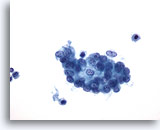

Figure 14

Peritoneal wash: Benign mesothelial cells in a cluster. 40X

Figure 14

Peritoneal wash:

Benign mesothelial cells in a cluster.

40X

Benign mesothelial cells from a peritoneal washing may also appear rounded up into a more three-dimensional group with some overlap. Close examination reveals uniform cells with benign nuclear features.